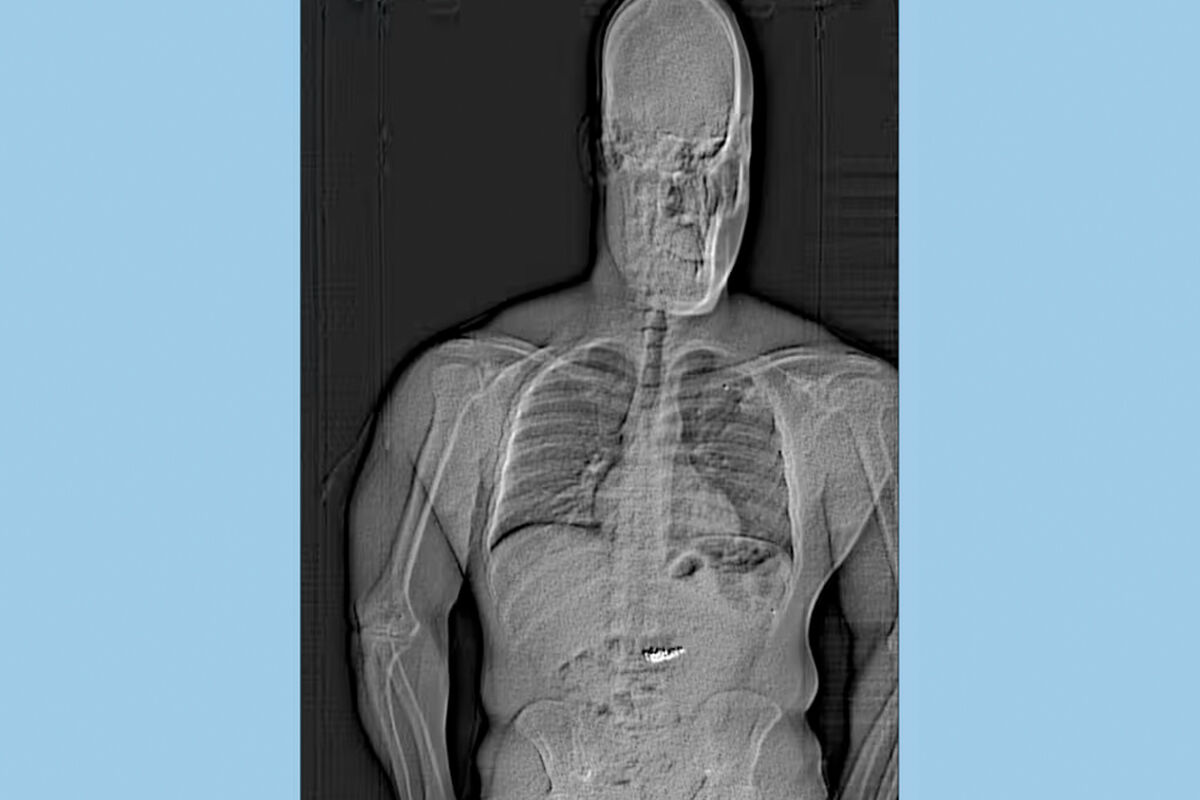

Подозреваемого удалось вскоре задержать. На сканировании, куда отправили Джейтана Гилдера, выяснилось, что в его желудке есть инородные предметы.

«Позже, после того как бриллианты были удалены из его организма, мы смогли отвезти их в Tiffany & Co., где их очистили, и главный ювелир подтвердил, что надпись и серийные номера соответствуют украденным изделиям», — отметили в полиции.